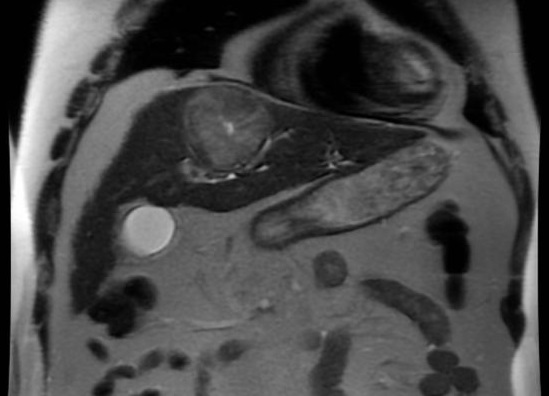

Image d'une carcinome

hepatocellule du foie droit en aspect une masse

nodulaire , hypersignale . Foie est en

cirrhose et ascite . Image IRM en T2 |